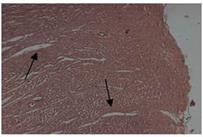

Fig. 1: Cholesterol control rat |

Fig. 1-4: Histopathological changes such as myocardial degeneration and inflammation of aorta occurred in rats during high fat diet intoxication and prevention by the treatment with methanolic (500 mg/kg) and ethyl acetate extract (500 mg/kg) of bark of Cassia fistula when compared to the standard Atorvastatin (10 mg/kg). The slides were studied under 200x magnification

Since oxidation of LDL plays a significant role in atherogenesis, amelioration of oxidative stress is equally important as controlling or decreasing hyperlipidemia. When summarized with the above results, the imbalance between oxidative stress generation and antioxidants formation could occur after feeding a high cholesterol diet. Nevertheless, extracts could prevent this pathological process, which indicated its therapeutic and preventive effect on hepatosteatosis induced by high cholesterol diet. Histopathology examination of aorta has shown normal integrity of cell membrane was maintained. Myocardial degeneration and inflammation was decreased in the groups treated with methanolic and ethyl acetate extracts of Cassia fistula when compared to that of cholesterol control group (fig. 1, fig. 2, fig. 3 and fig. 4).

Extracts were capable of potentially decreasing atherogenic Index and have increased the percentage protection. Superoxide dismutase and glutathione peroxidase levels have increased in the groups treated with extracts. Histopathology studies showed that the damage i.e. myocardial degeneration and inflammation that is caused due to atherosclerosis was found to be recovered. Hence it can be concluded that methanolic and ethyl acetate extract of Cassia fistula has antihyperlipidemic and anti-atherosclerotic activity on rats fed on a high cholesterol diet.